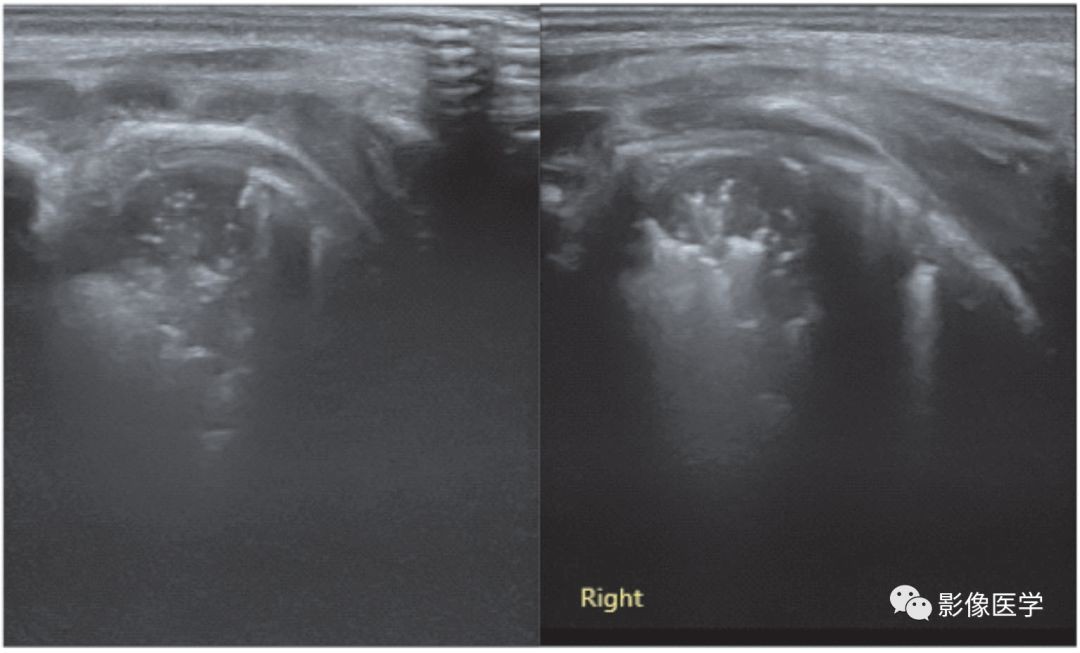

图6-13 呼吸机相关性肺炎(5)

患儿,男,胎龄37周,剖宫产分娩。因呼吸困难入院,肺脏超声呈RDS改变[因宫内感染(WBC 28.8×109/L,N 86%,杆状核粒细胞比例17%,CRP 24mg/L,PCT 85ng/mL)继发RDS],给予呼吸机治疗。出生后第5天,肺脏超声显示左肺(左:探头与肋骨垂直扫描)、右肺(右:探头与肋骨平行扫描)各见累及1个肋间的肺实变(箭头所示),左肺可见支气管充气征;右肺实变程度较深,支气管内充气已被全部吸收,呈低回声实变区。